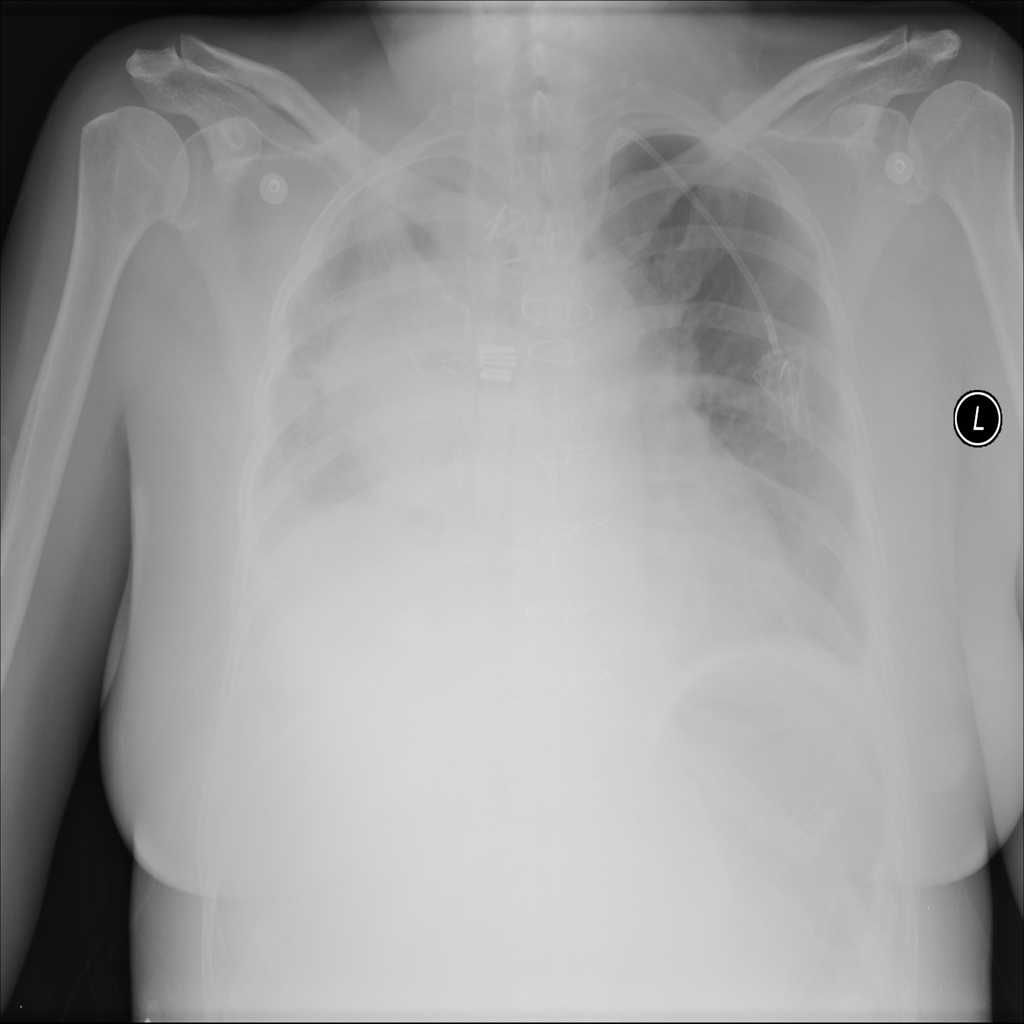

Mass

A mass is a larger focal opacity or lesion seen on the image. It is a descriptive finding that can have several causes and usually needs more imaging or clinical context to characterize.

PAT-50E5 · IMG-008Mass

PAT-50E5 · IMG-008

PA